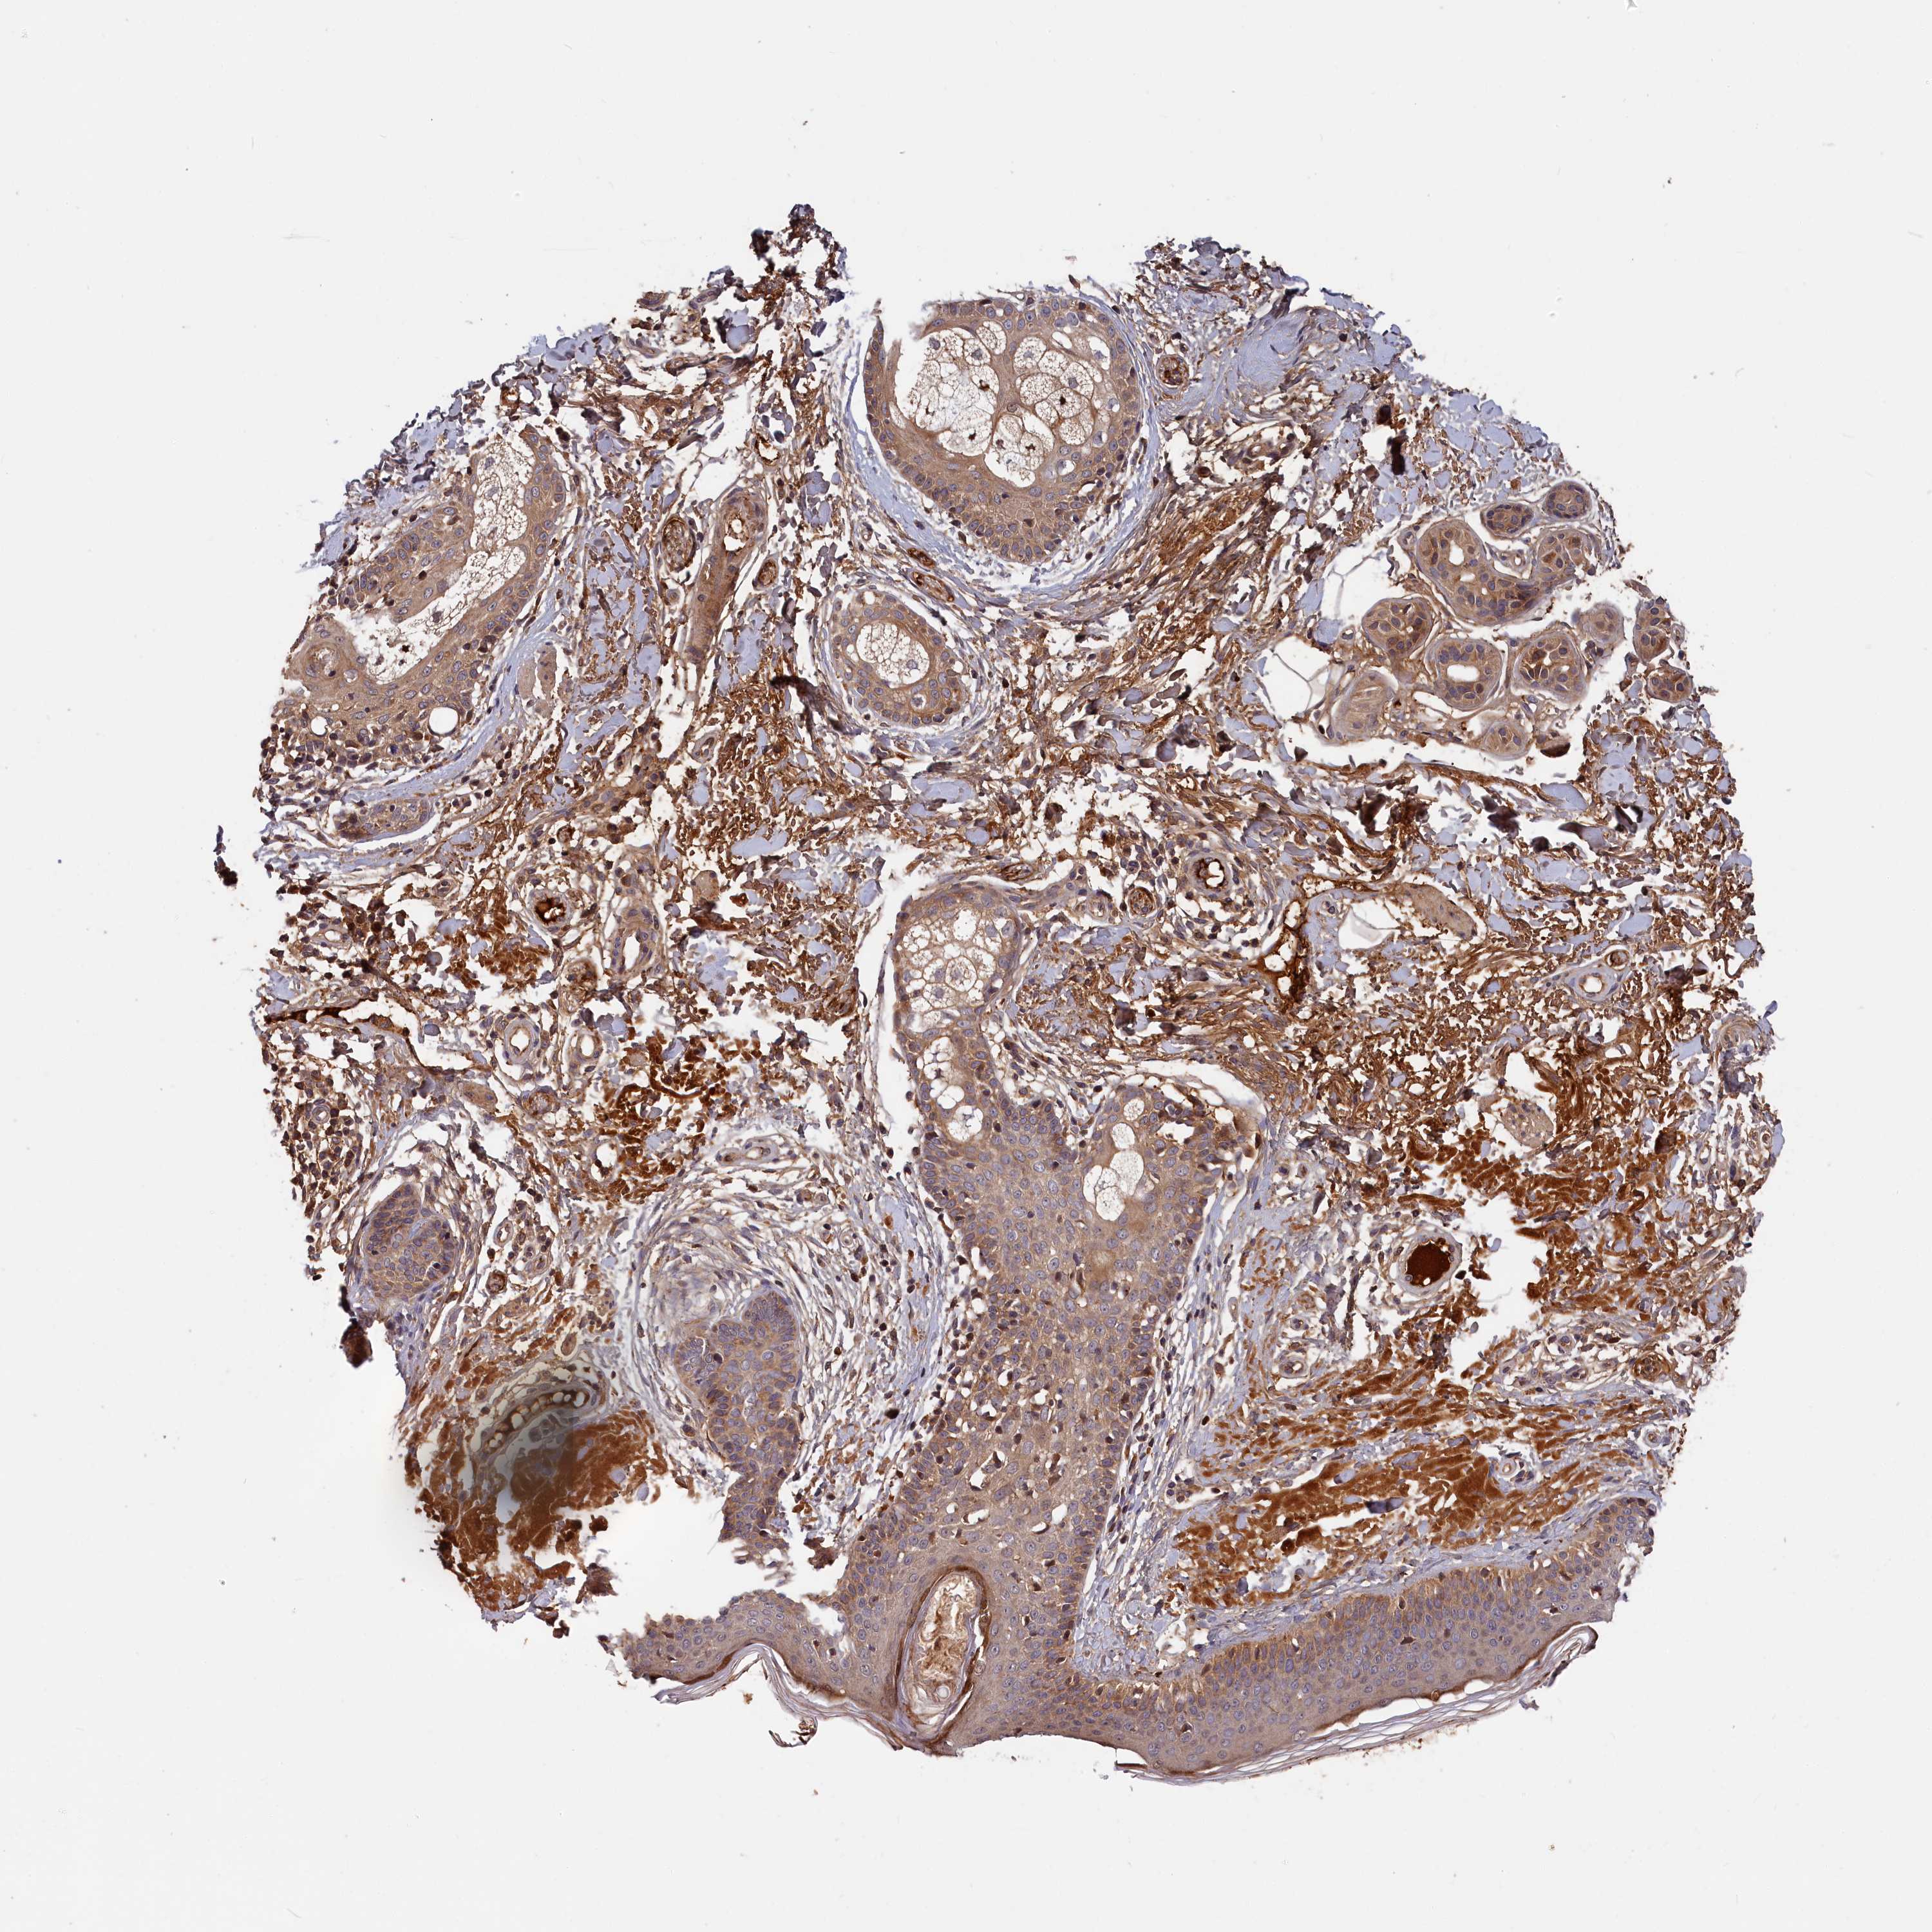

Basal cell and squamous cell cancer

SKIN CANCER - Protein expressioni

A mouse-over function shows sample information and annotation data. Click on an image to view it in a full screen mode. Samples can be filtered based on level of antibody staining by selecting one or several of the following categories: high, medium, low and not detected. The assay and annotation is described here.

Each image is clickable and will lead to virtual microscopy that enables deeper exploration of all samples and also displays staining intensity scores, fraction scores and subcellular localization as well as patient and tissue information for each sample.

Antibody HPA041639

Basal cell carcinoma

Squamous cell carcinoma, NOS